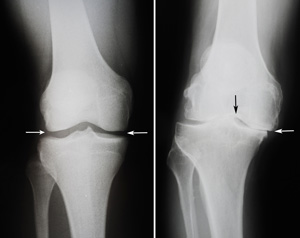

(Left) In this x-ray of a normal knee, the space between the bones indicates healthy cartilage (arrows). (Right) This x-ray of a knee that has become bowed from arthritis shows severe loss of joint space (arrows).